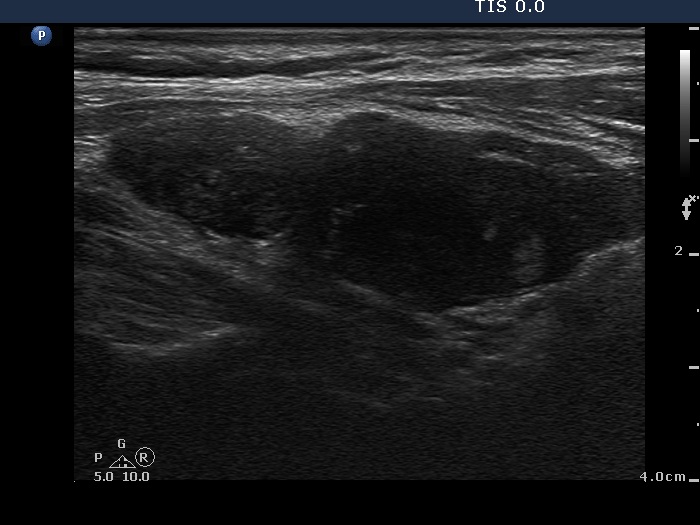

Ultrasonography: The right lobe was hypoechogenic, the left was moderately hypoechogenic. Both lobes were irregular in shape and were composed of several circumscribed areas surrounded with echonormal rim. The vascularization was significantly increased.

The sonographic pattern is specific. At first sight both lobes, particularly the right one seems to be nodular. First, the lobes are composed of a central hypoechogenic part surrounded with an echonormal rim, therefore it seems like the lobes were composed of a large hypoechogenic nodule. Second, connective tissue, perhaps a scar makes an impression in the ventral and in the dorsal part of the right and the left lobe, respectively. This makes an appearance as the lobes were composed of two nodules or one lesion with irregular lobulated and spiculated margins. In fact, the scar is responsible for the irregularities seen on the surface of the hypoechogenic mass, and regarding the hypoechogenic mass, the inclinations are the primary cause.